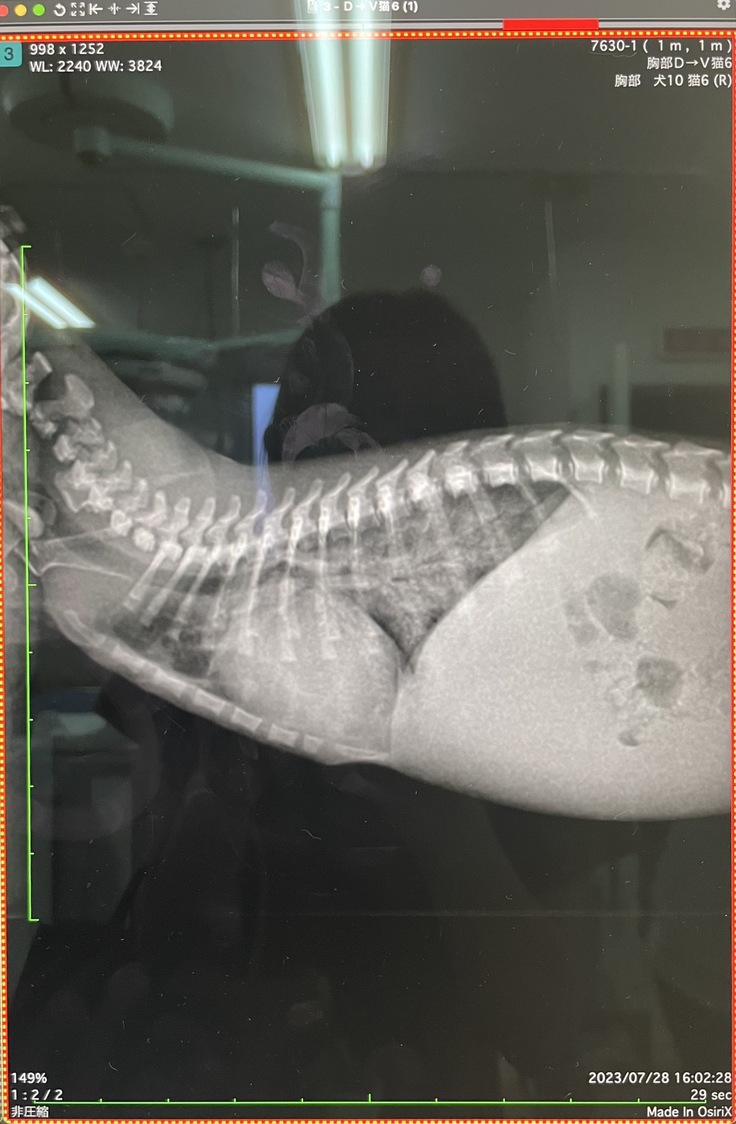

レントゲン写真を見せてもらいましたが、体が大きくなって、心臓もかなり大きくなっていました。肺も相変わらず、真っ白に…

↓1番左が今回のレントゲン

半日、利尿剤の点滴を打ってもらい、なんとか8/25に診てもらったときと同じくらいの状態(心臓の大きさや肺水腫)へ戻りました。